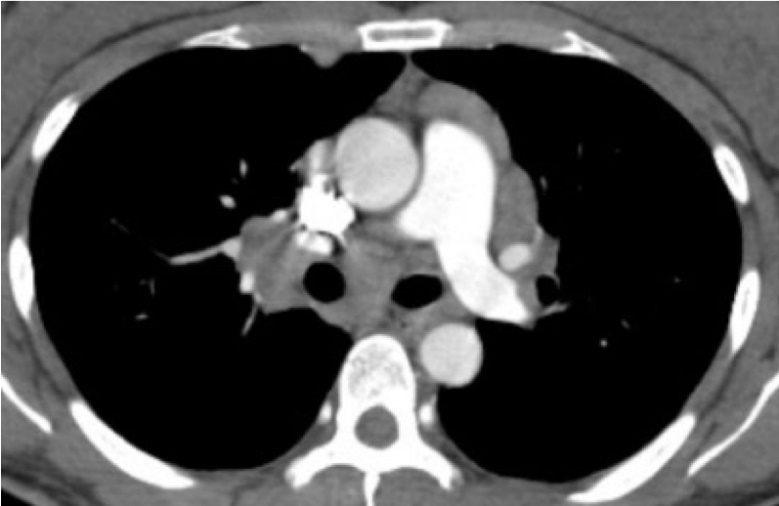

両側肺門リンパ節腫脹(BHL)と肺野病変

乾性咳があり、胸部画像で両側肺門リンパ節腫脹とともに肺野の異常がみられた25歳、男性。CTで両側肺のさまざまな部位に小粒状影が集族して円形様の広がる像を呈した。綿花状陰影と呼ばれる。